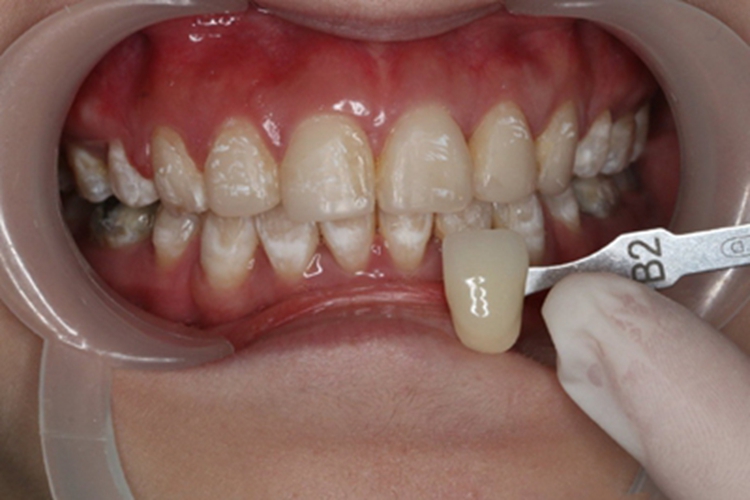

氟斑牙可表现为釉面光泽度改变,牙齿釉面失去光泽,不透明,可见白垩样线条、斑点、斑块。釉面也可出现不同程度的颜色改变,浅黄、深褐色或黑色,着色范围可有细小斑点、条纹、斑块,直至布满大部釉面。